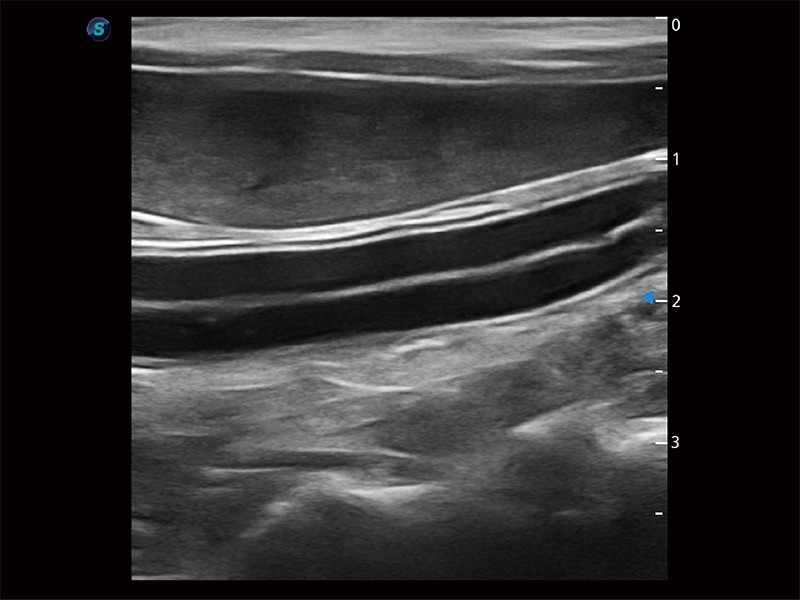

高性能和先進(jìn)的臨床應(yīng)用工具可以為動物醫(yī)生提供臨床信心。ProPet 80 搭載了先進(jìn)的腹部和淺表應(yīng)用工具,幫助醫(yī)生在日常臨床實踐中發(fā)揮前所未有的作用。

為精細(xì)結(jié)構(gòu)及組織邊緣提供高清晰度的圖像和更大的成像視野。幫助減輕醫(yī)生的用眼疲勞,快速精準(zhǔn)獲得測量的數(shù)據(jù)。

ProPet 80 全新的動物超聲智能軟件和豐富的探頭群,為動物醫(yī)生提供了高清晰度和精細(xì)分辨率的圖像,無論在寵物、馬科、畜牧還是實驗室動物等應(yīng)用中都可以輕松應(yīng)對,為您的日常工作帶來滿意的體驗。